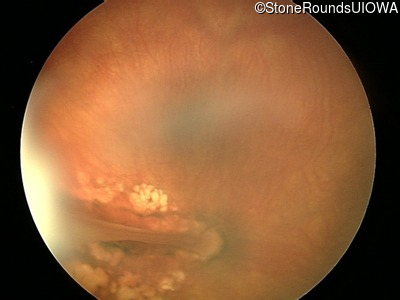

Visit at age: 23 months

Fundus Photography - Left - CUSM

Exemplar